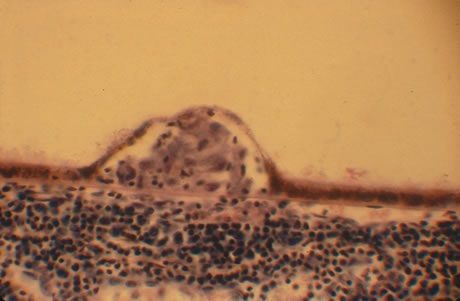

Classic histopathology consists of caseating granulomatous inflammation in a zonal distribution. The noncaseating tubercle may be present but is less specific (Fig. 18). The organism is acid-fast, meaning that it does not decolorize with acid alcohol after staining with basic fuchsin, appearing as bright red, long thin rods. A definitive laboratory diagnosis of intraocular tuberculosis may be made via anterior chamber tap, vitreous or chorioretinal biopsy depending on the site of inflammation. The PCR may be helpful in making the diagnosis.

Fig. 18. Histopathologic examination of an enucleated eye demonstrates a caseating focus in the choroid.